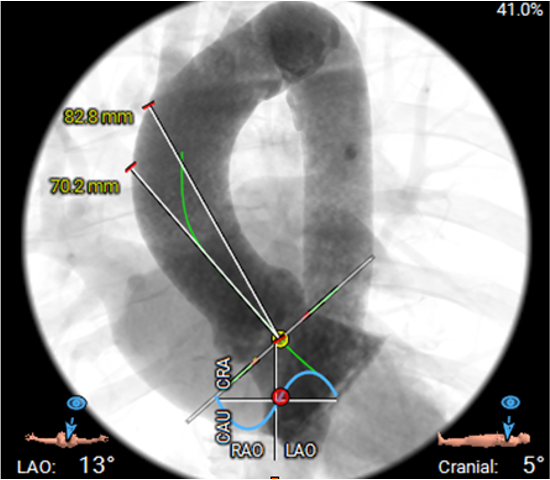

b.使用自膨胀瓣膜,瓣环水平到升主动脉穿刺点大于70mm;

TAVR 手术策略:

①由于选择升主动脉入路,常规经股动脉手术器械较长,增加操作风险,选择25cm、20F血管鞘建立入路通道。

②选用20mm球囊预扩,TaurusElite AV26瓣膜,初始释放高度为瓣环0mm, 目标定位瓣下2mm。